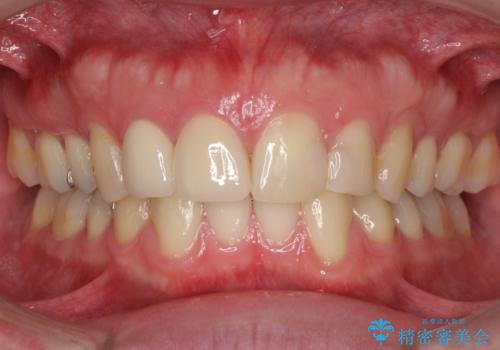

当初は1番目立つ1本だけをご希望でしたが、相談の結果、隣の歯(神経が抜いてあり金属が入っている歯)と2本同時に製作することになりました。

上の前歯など審美性の要求が高くなる部位については、数本同時に製作することで色をそろえることが可能です。

患者様は前歯の見た目の改善を主訴にご来院されました。上の前歯6本とも古いつめものがつぎはぎになっていましたが、まずは1番目立つところを治すことをご希望でした。相談の結果、今回は2本できれいになるように工夫しました。

患者様には大変満足して頂きました。